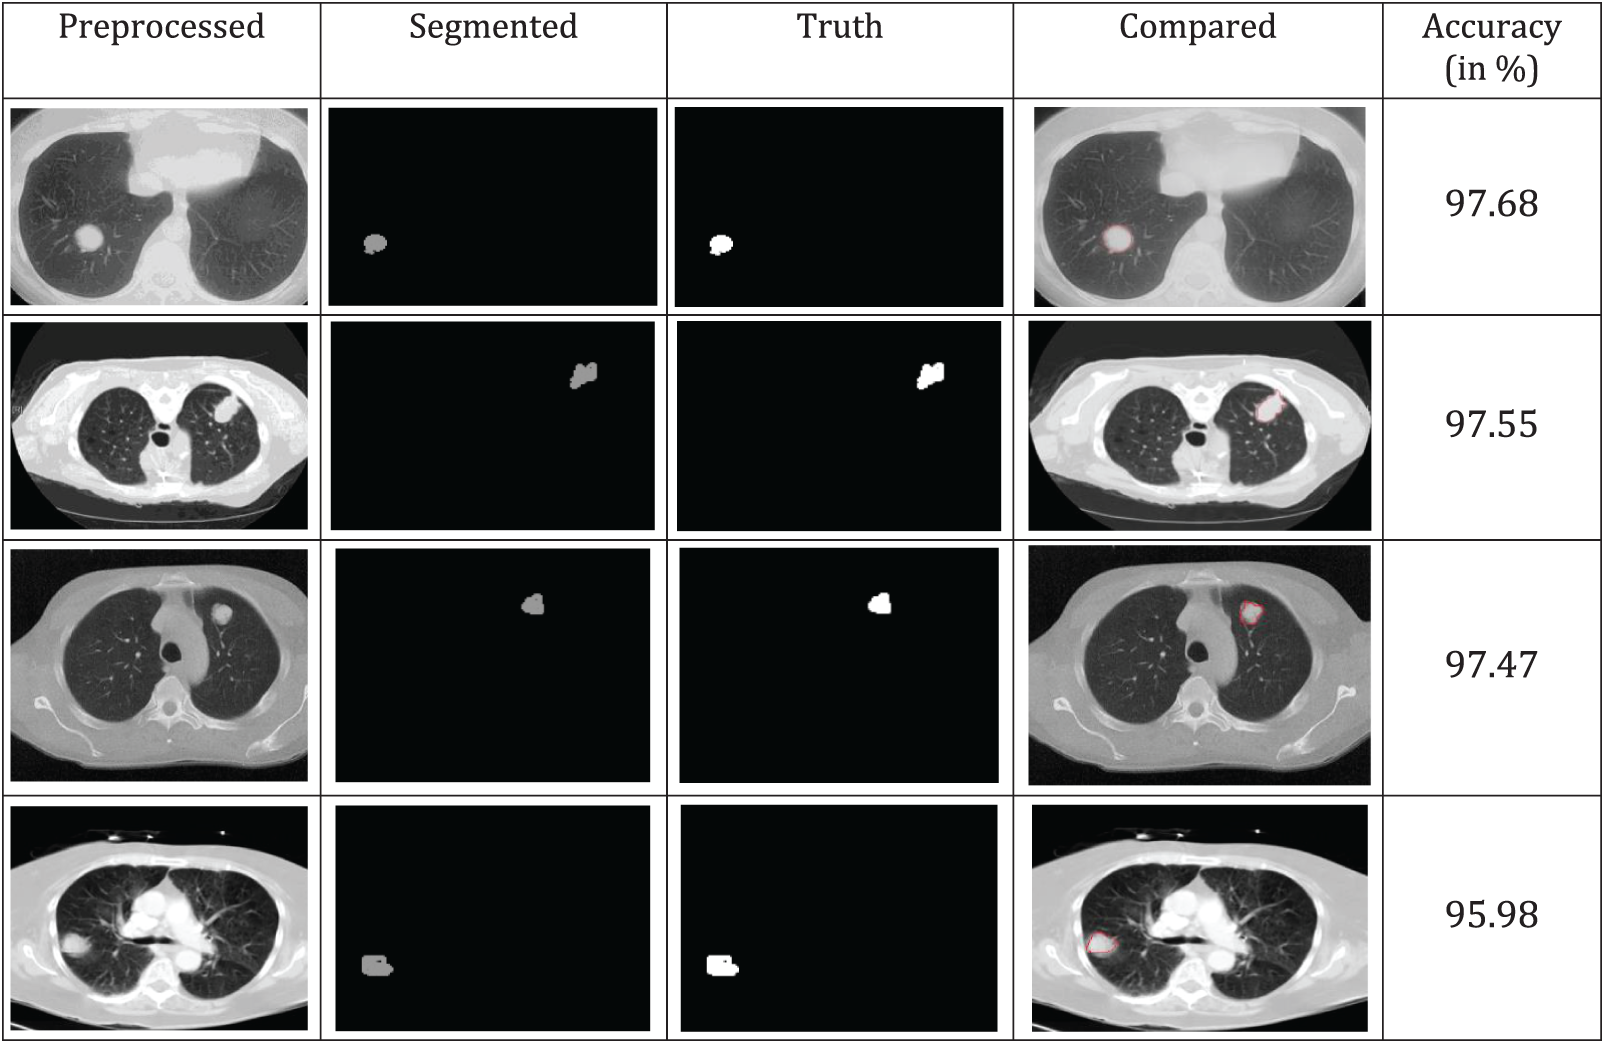

A comparison of the accuracy of various segmented image techniques in the real world is shown in Fig. 6. According to the results, the threshold has better accuracy. The similarity between individual pixels in an image is used as a basis for the production of distinct segmented regions, which draws attention to relatively small areas. To achieve a higher level of precision, several morphological techniques may cut off a portion of the image without completely obliterating it. The categorization accuracy and ground truth image comparison yield higher values of more than 95%, as shown in Fig. 6.

Figure 6: Segmentation and truth image comparison